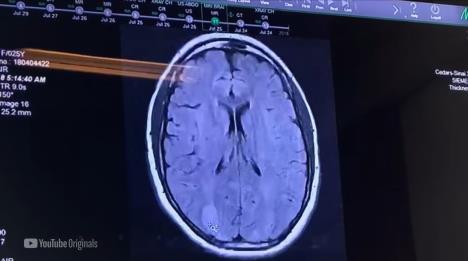

"Imala sam tri moždana udara, imala sam infarkt. Lekari su tada rekli da mi je ostalo pet do 10 minuta života", rekla je Demi Lovato (28) u dokumentarcu u najavi dokumentarne serije "Dancing With The Devil" ("Plesa sa đavolom"), u kojem njena prijateljica kaže: "Da li pričamo o he**inu . Da li o tome pričamo?".

"Imam oštećenje mozga i danas se borim sa posledicama. Ne vozim automobil jer imam problem sa vidom", rekla je i dodala je da je dugo imala poteškoće sa čitanjem.

"Zaista je bila velika stvar kada sam uspela da pročitam knjigu, recimo, dva meseca kasnije jer mi je vid bio toliko zamagljen", istakla je.